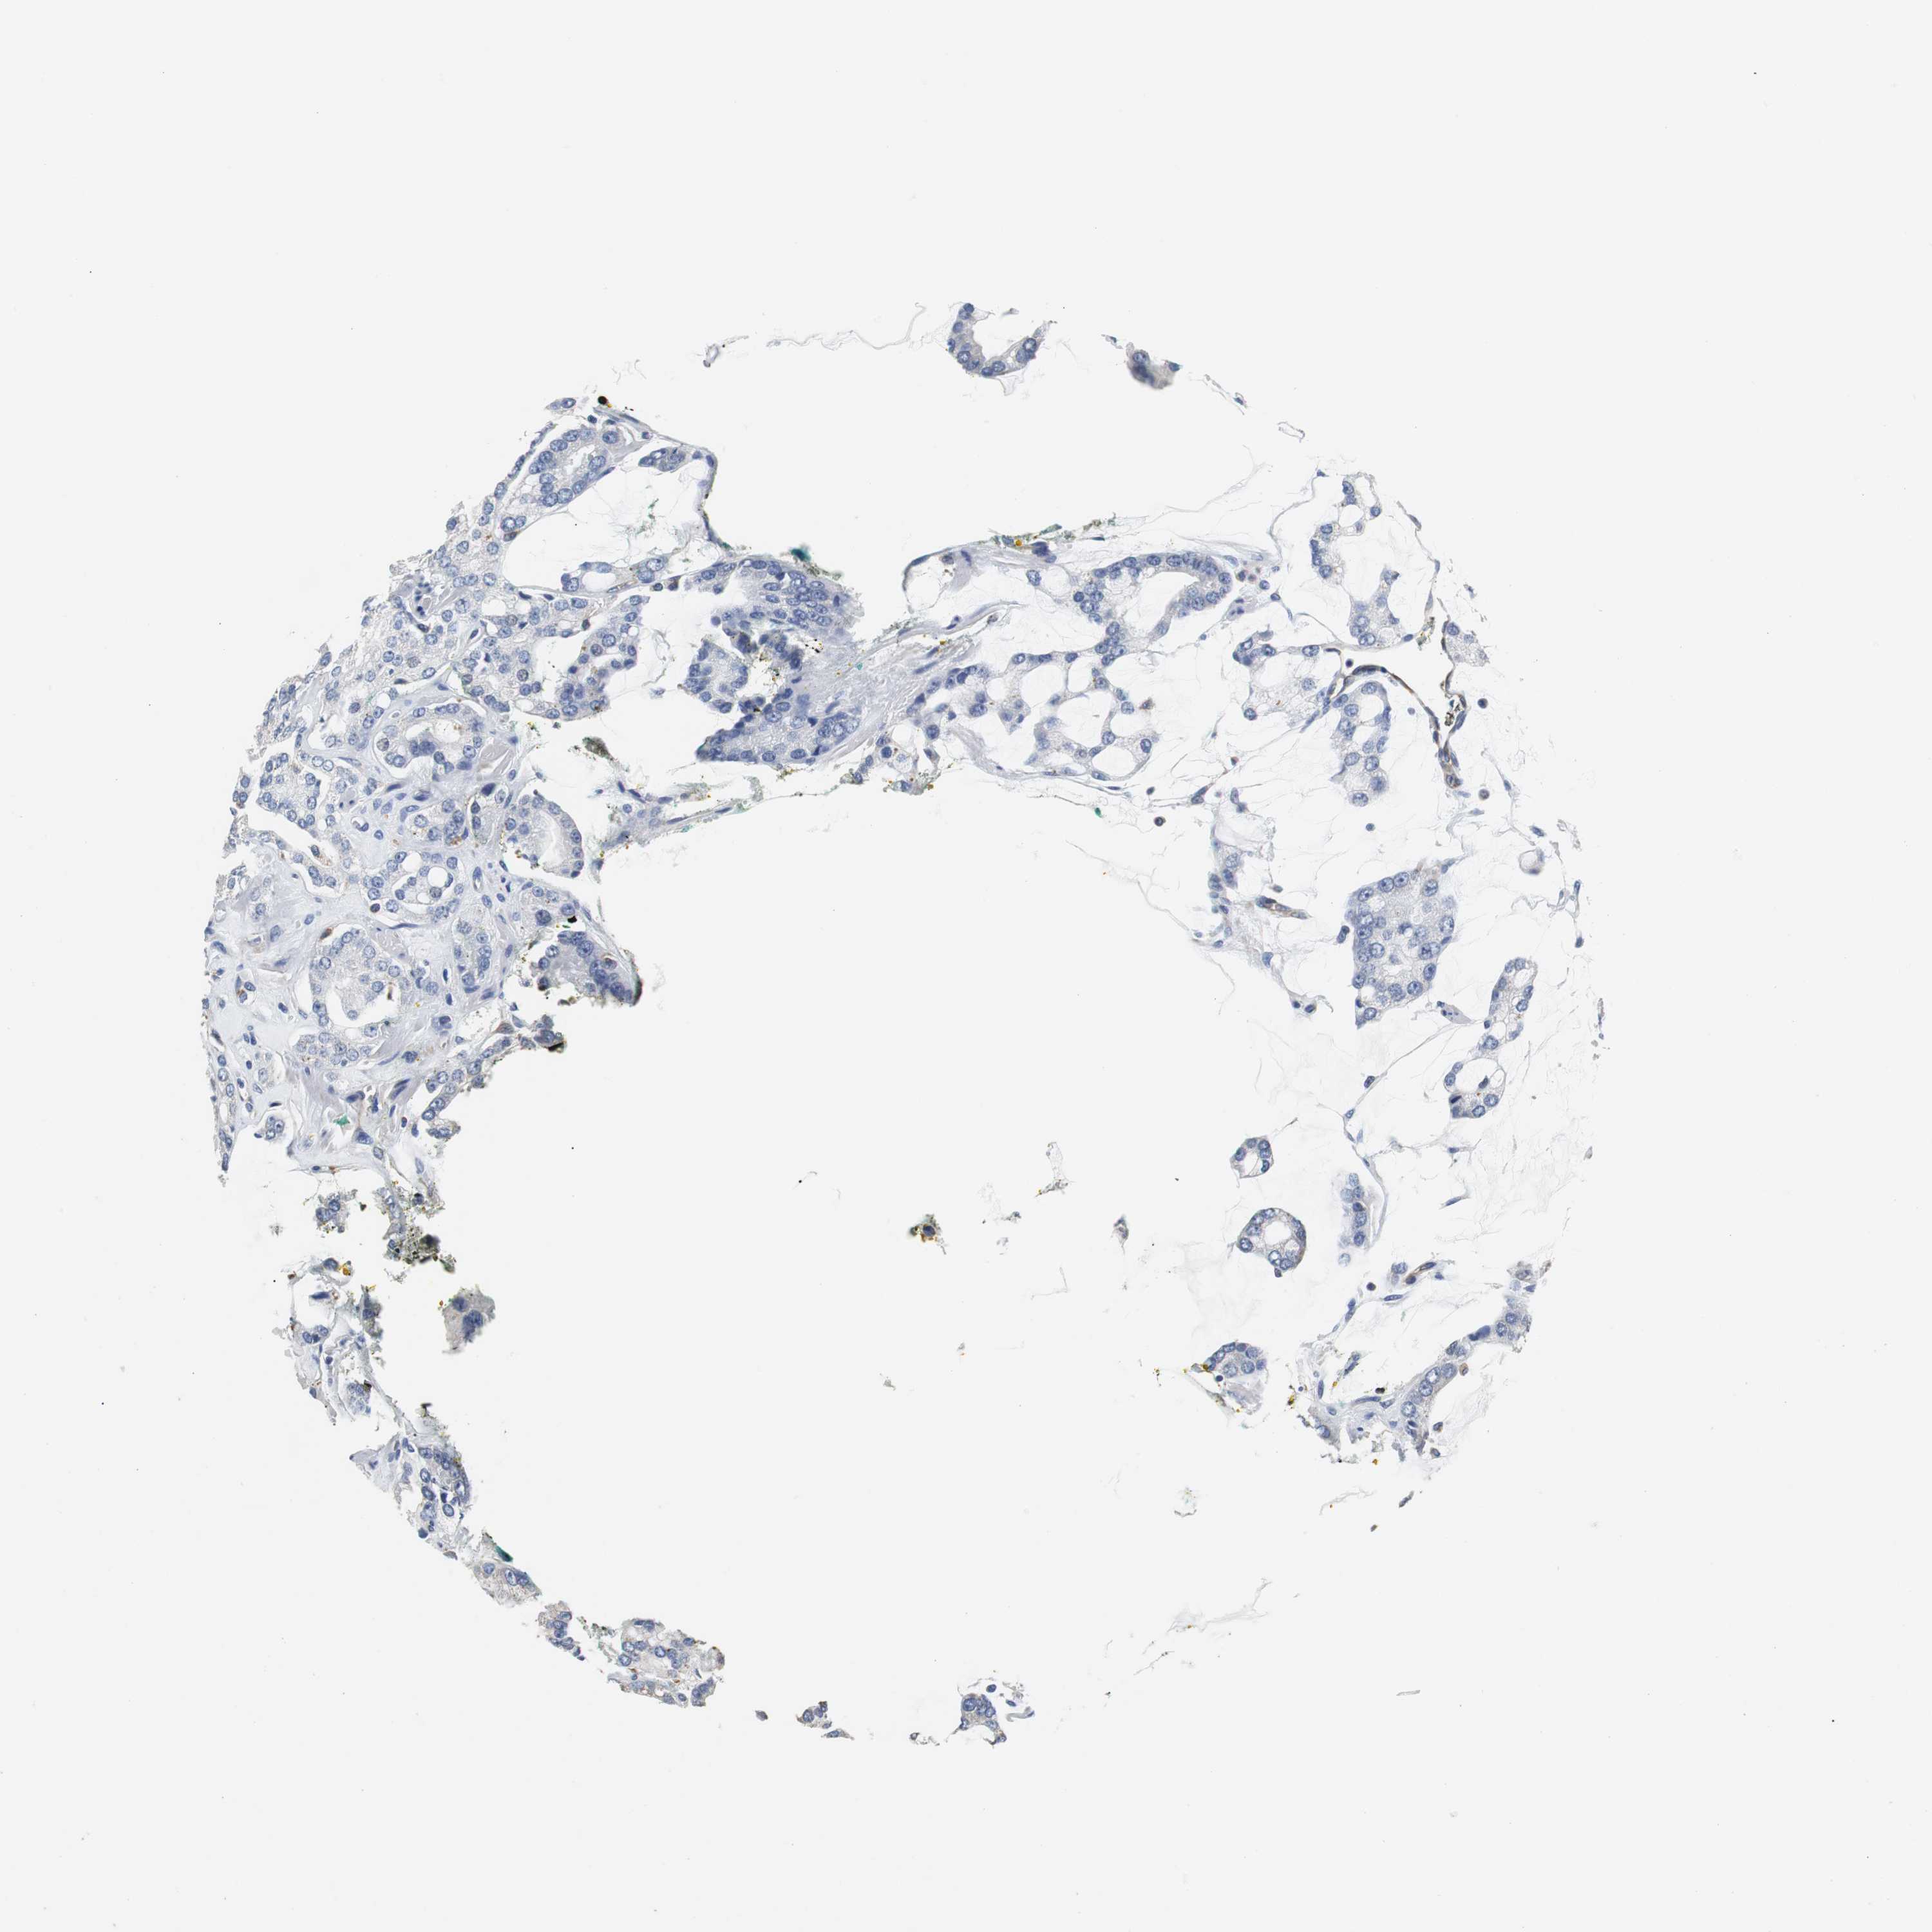

PROSTATE CANCER - Protein expressioni

A mouse-over function shows sample information and annotation data. Click on an image to view it in a full screen mode. Samples can be filtered based on level of antibody staining by selecting one or several of the following categories: high, medium, low and not detected. The assay and annotation is described here.

Antibody stainingi

Antibody staining in the annotated cell types in the current human tissue is reported as not detected, low, medium, or high, based on conventional immunohistochemistry profiling in selected tissues. This score is based on the combination of the staining intensity and fraction of stained cells.

Each image is clickable and will lead to virtual microscopy that enables deeper exploration of all samples and also displays staining intensity scores, fraction scores and subcellular localization as well as patient and tissue information for each sample.

Antibody HPA006277

Antibody HPA006507

Antibody CAB017027

Staining

High

Medium

Low

Not detected

Intensity

Strong

Moderate

Weak

Negative

Quantity

>75%

75%-25%

<25%

None

Location

Nuclear

Cytoplasmic/membranous

Cytoplasmic/membranous,nuclear

Adenocarcinoma, High grade

Adenocarcinoma, Low grade